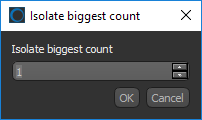

- Right-click the region of interest in the Data Properties and Settings panel and then choose Process Islands > Isolate (6-connected) nth First Biggest in the pop-up menu.

- Enter 1 in the Isolate Biggest Count dialog and then click the OK button.

All unconnected objects that are smaller than the largest object in the region of interest are removed from the ROI (see Processing Islands for more information about this feature).